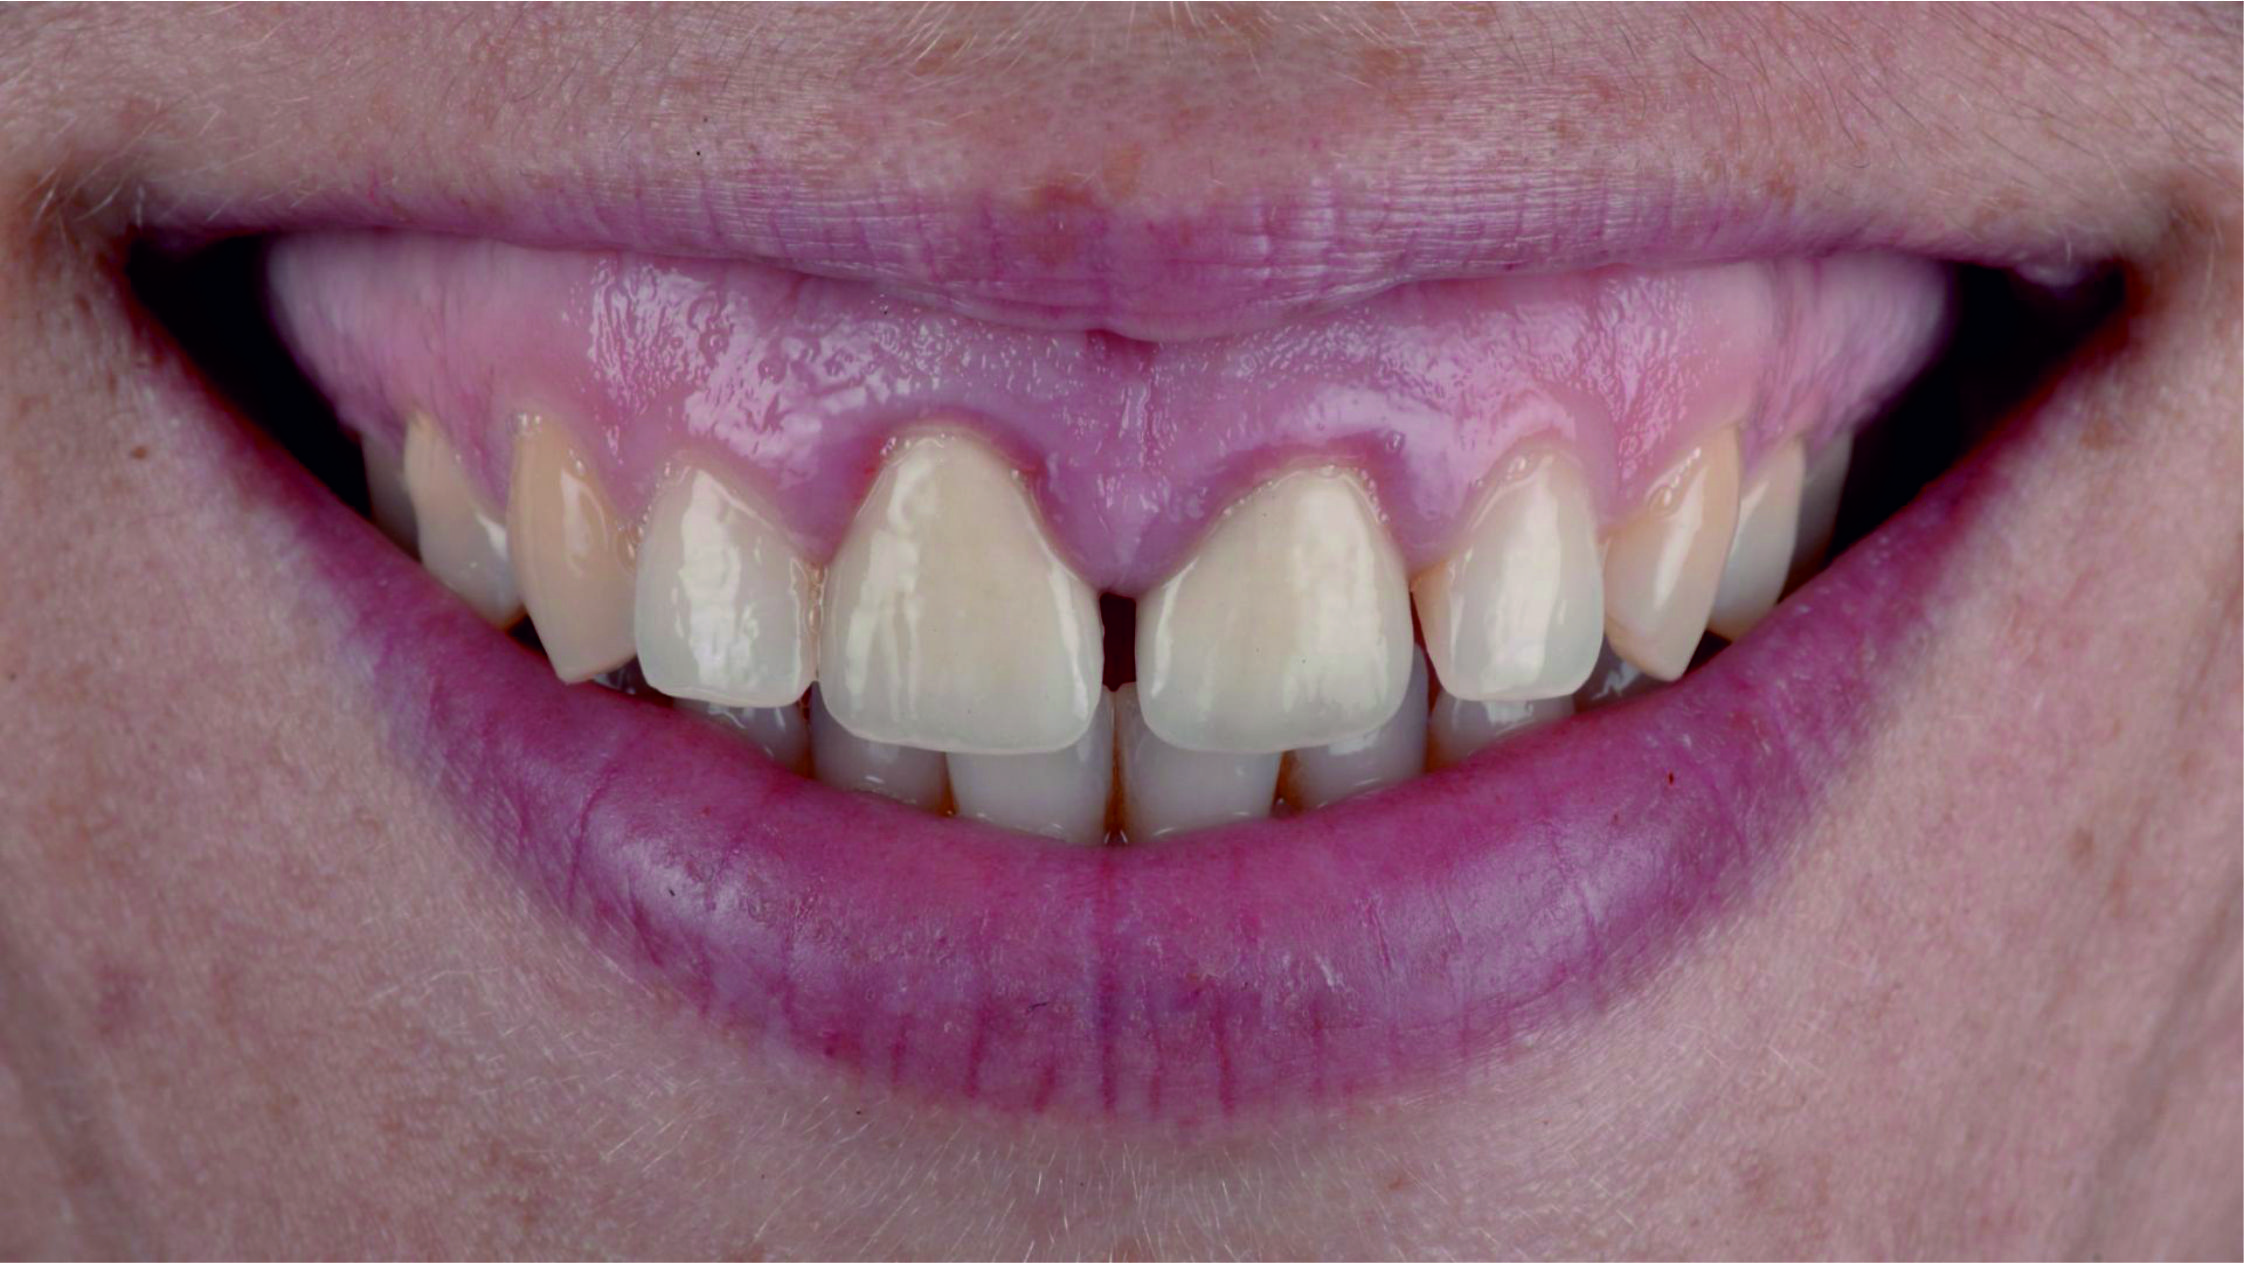

Фото 2. Через високо розташовану лінію посмішки можна припустити, що будь-яка вада після лікування обов'язково буде дуже добре помітною.